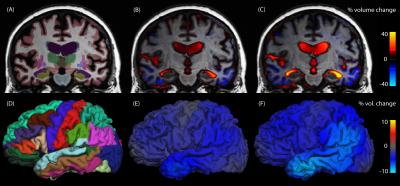

In a study that promises to improve diagnosis and monitoring of Alzheimer's disease, scientists at the University of California, San Diego have developed a fast and accurate method for quantifying subtle, sub-regional brain volume loss using magnetic resonance imaging (MRI). The study will be published the week of November 16 in the Proceedings of the National Academy of Sciences ( PNAS ).

By applying the techniques to the newly completed dataset of the multi-institution Alzheimer's Disease Neuroimaging Initiative (ADNI), the scientists demonstrated that such sub-regional brain volume measurements outperform available measures for tracking severity of Alzheimer's disease, including widely used cognitive testing and measures of global brain-volume loss.

The general pattern of brain atrophy resulting from Alzheimer's disease has long been known through autopsy studies, but exploiting this knowledge toward accurate diagnosis and monitoring of the disease has only recently been made possible by improvements in computational algorithms that automate identification of brain structures with MRI. The new methods described in the study provide rapid identification of brain sub-regions combined with measures of change in these regions across time. The methods require at least two brain scans to be performed on the same MRI scanner over a period of several months. The new research shows that changes in the brain's memory regions, in particular a region of the temporal lobe called the entorhinal cortex, offer sensitive measures of the early stages of the disease.

"The technique is extremely powerful, because it allows a researcher to examine exactly how much brain-volume loss has occurred in each region of the brain, including cortical regions, where we know the bad proteins of Alzheimer's disease build up," said study co-author James Brewer, MD, PhD, a neurologist and assistant professor in the Departments of Radiology and Neurosciences at UC San Diego. "We are particularly excited to use the techniques in new clinical trials, but also to reexamine old clinical trial data where global measures of brain shrinkage were applied. These new findings suggest that such global measures are less sensitive than regional measures for detecting the changes specific to Alzheimer's disease – the changes these drugs are targeting."